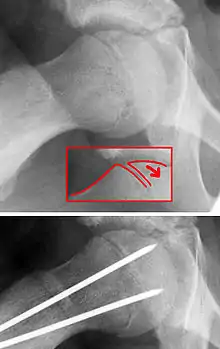

X-ray showing a slipped capital femoral epiphysis, before and after surgical fixation. | |

The diagnosis requires x-rays of the pelvis, with anteriorposterior (AP) and frog-leg lateral views.[11] The appearance of the head of the femur in relation to the shaft likens that of a "melting ice cream cone", visible with Klein's line. The severity of the disease can be measured using the Southwick angle.

The disease can be treated with external in-situ pinning or open reduction and pinning. Consultation with an orthopaedic surgeon is necessary to repair this problem. Pinning the unaffected side prophylactically is not recommended for most patients, but may be appropriate if a second SCFE is very likely.[11]

Once SCFE is suspected, the patient should be non-weight bearing and remain on strict bed rest. In severe cases, after enough rest the patient may require physical therapy to regain strength and movement back to the leg. A SCFE is an orthopaedic emergency, as further slippage may result in occlusion of the blood supply and avascular necrosis (risk of 25 percent). Almost all cases require surgery, which usually involves the placement of one or two pins into the femoral head to prevent further slippage.[12] The recommended screw placement is in the center of the epiphysis and perpendicular to the physis.[13] Chances of a slippage occurring in the other hip are 20 percent within 18 months of diagnosis of the first slippage and consequently the opposite unaffected femur may also require pinning.

The risk of reducing this fracture includes the disruption of the blood supply to the bone. It has been shown in the past that attempts to correct the slippage by moving the head back into its correct position can cause the bone to die. Therefore the head of the femur is usually pinned 'as is'. A small incision is made in the outer side of the upper thigh and metal pins are placed through the femoral neck and into the head of the femur. A dressing covers the wound.